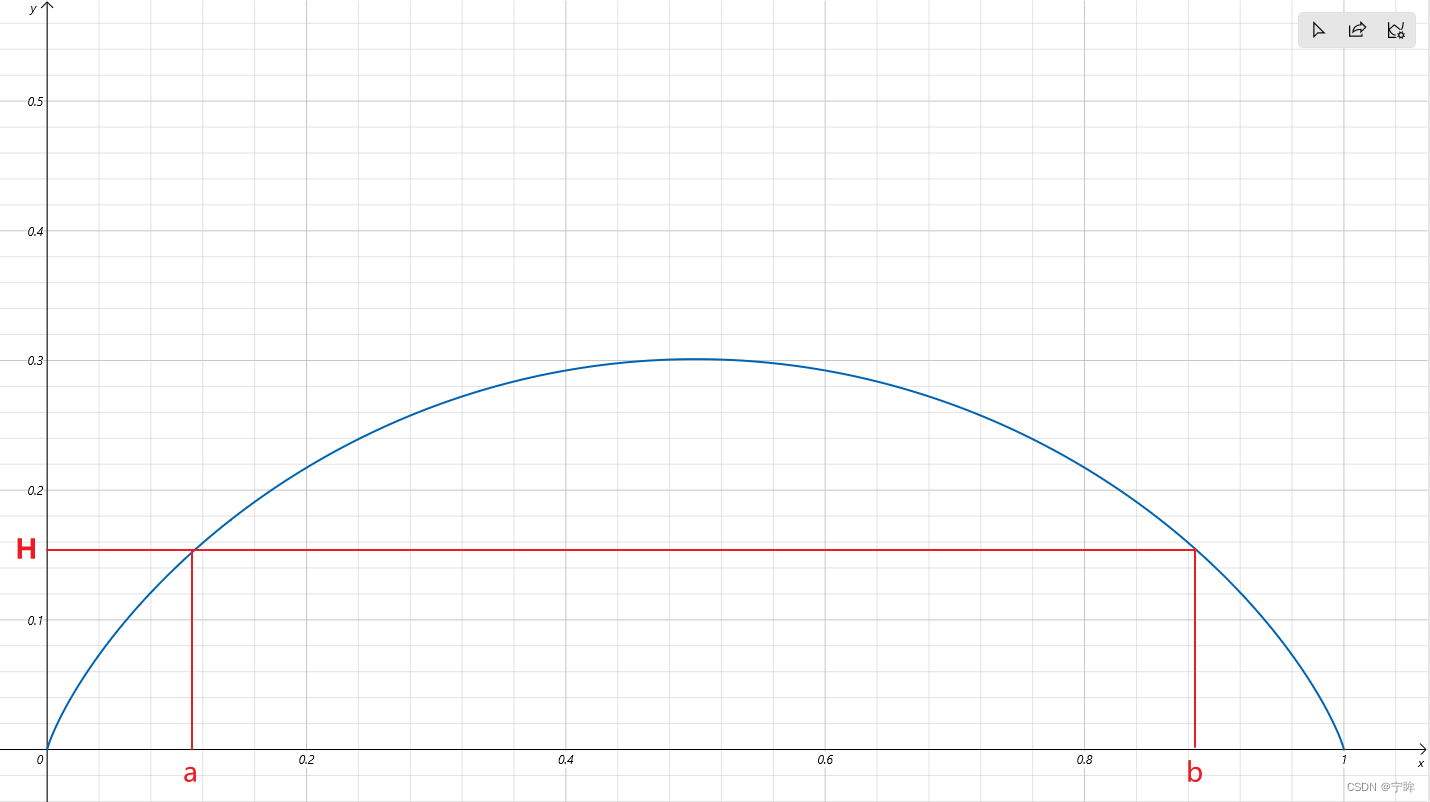

下图是y = - [xlog(x)+(1-x)log(1-x)]的曲线

x在0和1之间,y随着x的增加先递增后递减。y表示不确定度,y越大的位置,不确定度越高。选定一个阈值H,过滤掉 y > H的区域,那么相当于只选择了(0,a)和(b,1)的区域,也就是不确定度低的区域。通俗的理解,以二分类为例(随机变量X要么是A类,要么是B类,非黑即白),如果X是A类的概率很小或者很大,我们可以说X是比较确定的,而X是A类的概率在0.5左右时,我们就说事件X是不确定的。